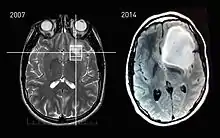

و هذه بعض التصويرات بالرنين المغناطيسي التي تكشف عن بعض الحالات الشائعة من الورم النجمي :

تصوير بالرنين المغناطيسي، يبين تطور الورم النجمي على مدى سبع سنوات.